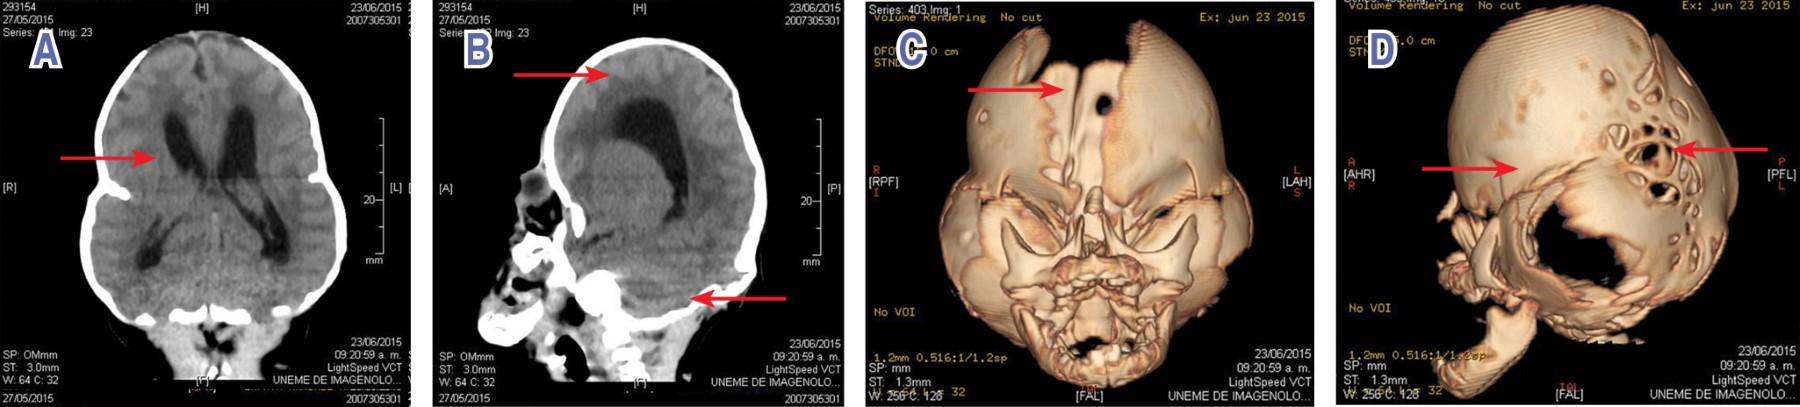

Introduction: Pfeiffer syndrome is an autosomal dominant disorder with an incidence of 1 in 100,000 newborns, which is characterized by craniosynostosis, besides hand and foot malformations. Clinical case: 26-day-old female, daughter of first pregnancy; 18-year-old mother and 23-year-old father, without consanguinity or inbreeding. It was obtained at term. Physical examination: cloverleaf skull, wide anterior fontanelle, wide forehead, bitemporal narrowing, hypoplastic supraorbital arches, and bilateral ocular proptosis. Upper extremities: broad thumbs, bilateral fifth finger clinodactyly. Lower extremities: broad first toes, bilateral fifth toe clinodactyly. Skull CT scan: fusion of the lambdoid, sagittal, and coronal sutures, ventricular asymmetry, with decreased density of the brain parenchyma, and cerebellar hypoplasia. At 35 days of life the patient died. Conclusion: Clinical and prognostic spectrum of patients with Pfeiffer syndrome is wide and depends on the type of mutation in FGFR1 and FGFR2 genes. These patients require multidisciplinary management.

Figure 1